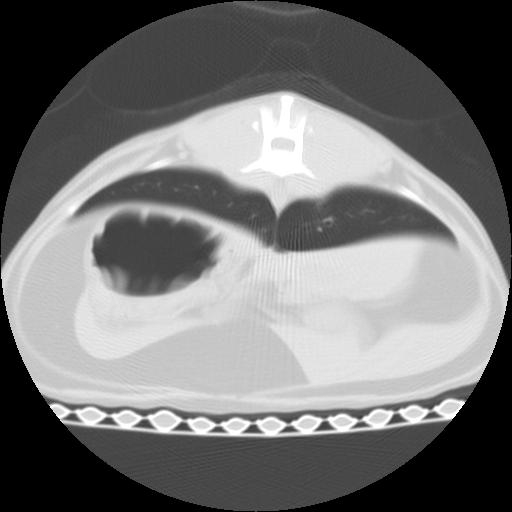

The CT images show that there is severe thickening of the lobar bronchi to the cranial lobes, and also of the proximal portions of the mainstem bronchi. The right cranial lobar bronchus is bronchiectatic, and a large intraluminal soft tissue occlusion is identified peripherally. Multiple other peripheral airways reveal intraluminal soft tissue accumulation. The right middle lobe is collapsed. There are multifocal patchy areas of interstitial and peribronchial infiltrates throughout all lung lobes, but most severe within the caudal lobes.

On the CT images, the right main stem bronchus dilated in periphery in comparison with the opposite side. The conccurent alveolar pattern in X-ray is also confirmed around the heart.